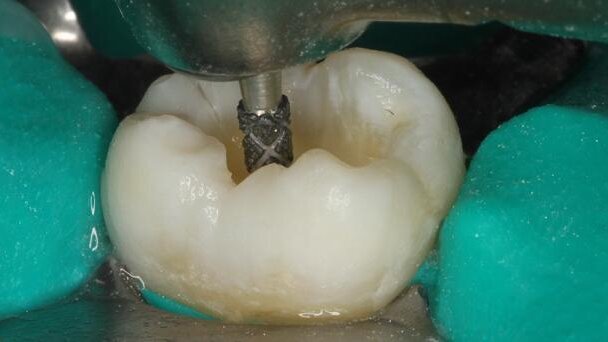

Access through the enamel is created with a Great White Gold #2 carbide [29] (Fig. 19) or a TDA #849 diamond high-speed bur (Fig. 20; both from SS White).[30] Once the deep decay has been exposed, SmartBurs II selectively removes the soft carious (infected) dentine (Fig. 21). The structure of SmartBurs II is designed to determine the preparation end-point automatically; any further rotation of the bur in the cavity simply abrades the bur, not the dentine. This leaves the harder, remineralisable (affected) dentine covering the pulp chamber intact (Fig. 22).